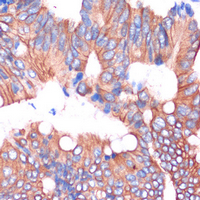

• Immunohistochemical analysis of Cingulin staining in human colon cancer formalin fixed paraffin embedded tissue section. The section was pre-treated using heat mediated antigen retrieval with sodium citrate buffer (pH 6.0). The section was then incubated with the antibody at room temperature and detected using an HRP conjugated compact polymer system. DAB was used as the chromogen. The section was then counterstained with haematoxylin and mounted with DPX.